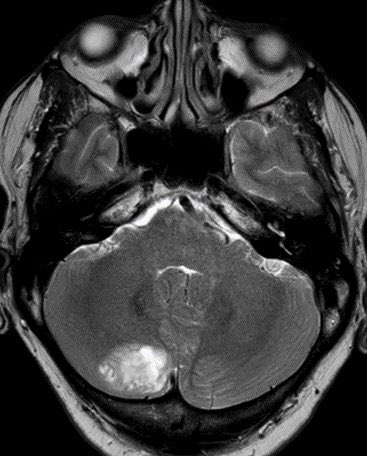

⭐️ Companion case of Lhermitte-Duclos - Unilateral cerebellar mass w/ striations due to hyperintense expanded fovea on T2 w/ normal signal intervening parenchyma

Typically there is no to little enhancement and high signal on DWI due to T2 shine-through w/ high signal on ADC x.com

💡 Both Lhermitte-Duclos & Medulloblastoma SHH can have a striated appearance! Use DWI/ADC, density on CT, & enhancement to distinguish!